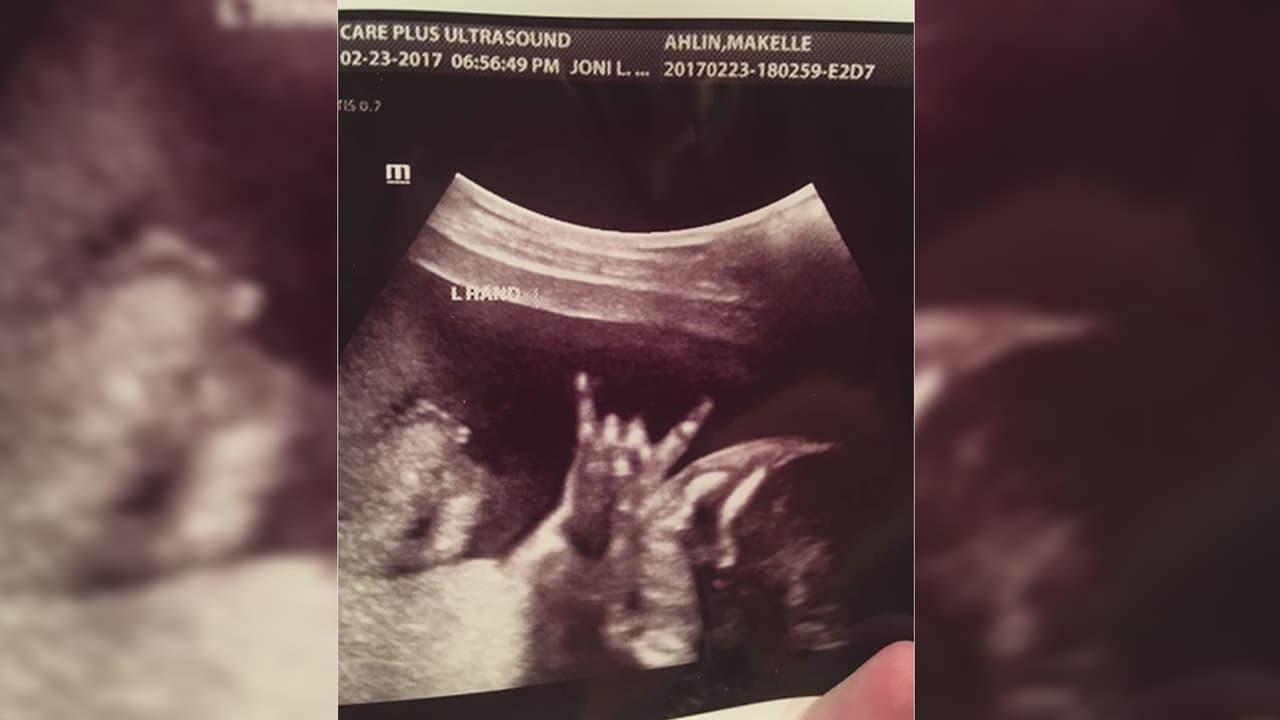

Los padres se sorprendieron cuando vieron el gesto del bebé durante un ultrasonido. Con una de sus manos hacía el tradicional saludo de los rockeros, y la imagen no ha dejado de ser compartida en redes sociales.